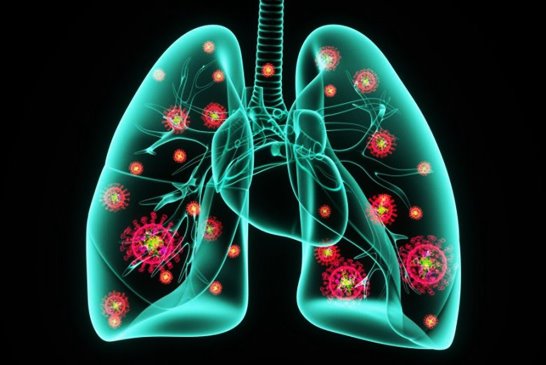

폐암 초기증상은 호흡관란, 지속적인 기침 및 가래, 흉통 등이 있으며, 조기발견과 정확한 진단이 중요합니다. 아래에서는 폐암 초기증상에 대해 자세히 알아보고 조기 발견할 수 있도록 도움이 되었으면 합니다.

폐암 예방법

흡연은 폐암의 가장 큰 원인 중 하나입니다. 담배를 피우지 않거나 금연하는 것이 폐암 예방에 가장 효과적입니다. 만약 흡연 중이라면 의사나 금연 전문가의 도움을 받아 금연 계획을 수립하는 것이 좋습니다.

실내 공기질을 개선하고 유해 물질로부터의 노출을 최소화하는 것이 중요합니다. 환기를 유지하고 공기 청정기를 사용하여 실내 공기를 깨끗하게 유지하는 등의 노력을 해야 합니다.